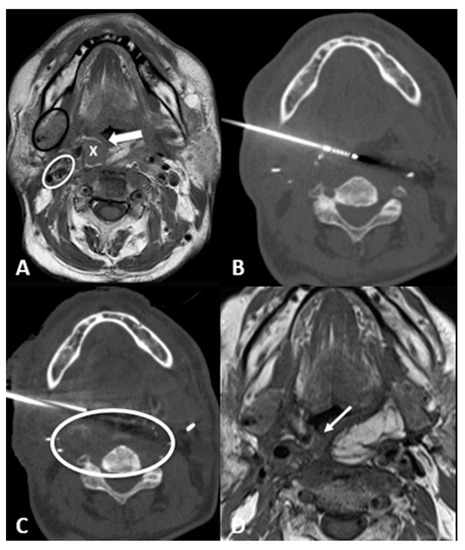

- Retromaxillary: In the case of a retromaxillary approach, the maxilla is used as a landmark. This approach is mostly used for lesions located in the masticatory space and the pharyngeal and laryngeal mucosa (Figure 1).

- Retromolar trigone: This is the space between the last molar and the mandibular condyle. It is a space without many vessels/nerves or vital structures; therefore, it represents a safe approach to treating pharyngeal and laryngeal lesions. Tongue positioning is mandatory, as it can flop backward against the ablation site resulting in frost injury: Forceps and a laryngoscope should be used to displace the tongue with gauze away from the ablation site to avoid this occurrence. In the case of tumors near the carotid artery, the patient can manifest severe hypotension and bradycardia during ablation. The presence of coils or metallic devices in a previously embolized carotid artery leads both to a loss of the cold-sink effect as well as a stimulation of the vagus nerve with thermal conduction down the carotid body (leading to the diving reflex). Cessation of cryoablation usually leads to spontaneous resolution (Figure 2).

- Transglandular: This is a very useful approach in case of lesions in the pharyngeal space and prevertebral space, crossing the submandibular gland to reach these locations (Figure 3).

- Transflap: Useful in the case of early local tumor recurrence, in patients who underwent previous surgery, and myocutaneous flap reconstruction (Figure 4). The myocutaneous flap is usually devoid of significant vascularity and vital structures and presents a safe trajectory once it has been grafted [13].